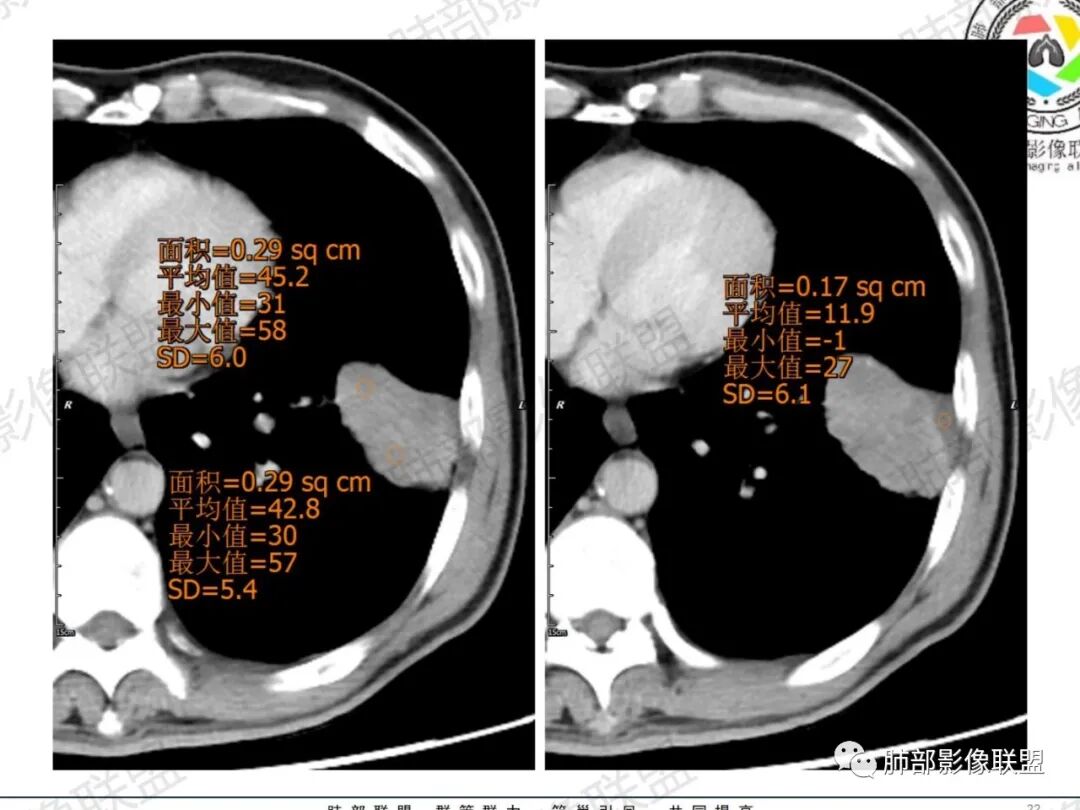

一切∮随缘:左肺下叶不规则肿块,边缘光滑,平直,局部彭隆,分叶,近端支气管堵塞,远端与胸膜相贴,平扫密度尚均匀,增强后不均匀强化,内部可见低密度坏死,胸膜下多发肺气肿,伴双肺散在光滑小结节,实验室肿瘤标志物高,考虑恶性:神经内分泌癌(大细胞),腺癌,鳞癌。

琦遇:恶性没有问题,肺气肿底子、病灶分叶、少许毛刺、叶间胸膜凹陷、部分边缘可见清晰的GGO、胸膜牵拉凹陷、局部胸水、近端支气管截断、部分支气管被推移、占位效应明显、强化特点为不均匀强化、内部有少许沼泽样低强化区,强化部分轻中强化为主、余肺可见转移性结节、左肺上叶似为囊腔型腺癌一枚,肿瘤标志物提示非小、神经内分泌,综合分析考虑大神泌、腺癌、腺鳞癌、鳞癌  同时左肺上叶囊腔型腺癌  肺转移

飞鹰行动:中年人,男性,胸疼入院,左肺下叶占位,张力较高,边界可见分叶,局部可见明显收缩性改变,增强病灶内部有延迟强化表现,考虑恶性病变,大细胞癌伴肺内转移或者囊腔样腺癌伴转移。

蕊:中老年男性,吸烟史,肺气肿背景,左肺上叶类圆形肿块影,边界清晰,边缘凹凸不平,有分叶,支气管进入阻断,临近胸膜栽赃,整体病灶膨隆,局部周围可以清晰ggo,临近叶间裂内凹,轻度强化,并可见多个低密度区,坏死可能,界线不清;肺内多结节,边缘光滑,考虑恶性伴转移,鳞癌、腺癌

傅昌瑜:中老年男性,肺气肿背景,右胸背疼痛1周。CEA、NSE、CYFRA—211升高。左上肺混合磨玻璃结节,内见较多空泡和扩张支气管。左下肺胸膜下肿块,边缘较光滑,深分叶,似有血管进入,与支气管关系不清,内见不均匀强化,见沼泽地样坏死,有胸膜栽赃。另两肺多发圆形小结节。考虑恶性并肺内转移,多原发可能性大,左上肺腺癌,左下肺病理难以判断,小细胞癌?鳞癌?

小锁:中老年男性,肺气肿背景,右胸背疼痛1周。CEA、NSE、CYFRA—211升高。左上肺混合磨玻璃结节,边界清楚,内见较多空泡。左下肺肿块,边缘清楚,深分叶,有血管和支气管进入,胸膜凹陷。另两肺多发圆形小结节。考虑双发原位癌,左上肺腺癌,左下肺大神泌或腺鳞癌可能,肺内转移。

蓝天白云:中年男性,肺气肿背景,左肺下叶肿块,边缘膨隆,有分叶,内有湖泊样坏死,有轻中度强化,局部胸膜栽赃,收缩力不强,周围见肺气肿征象。左肺上叶混合磨玻璃影,边界清楚,考虑都是恶性,左上肺iac,左下肺腺鳞癌,或大细胞肺癌可能。两肺多发结节,考虑转移

毛勤香:老年男性,肺气肿背景,左肺下叶肿块,分叶,边缘光滑,土豆块样,细支气管闭塞,增强轻度不均匀强化,似有坏死,左肺另见多发结节,淋巴结未见明显肿大,恶性确定,吸烟史,鳞癌破坏力强,侵袭力差,多原发的一般很少多于3个,故排后,首先考虑神经内分泌癌,局部血管穿行,鉴别淋巴瘤

周太狼:中年男性,吸烟、高血压史,肿瘤指标升高,肺气肿背景下,左肺下叶肿块影,分叶、膨隆、未跨叶裂,支气管截断,不均匀强化。另双肺多发结节及磨玻璃影,左肺上叶混合磨玻璃,内可见多发空泡影。整体考虑恶性,肺癌伴肺内转移,左下肺鳞癌?神经内分泌癌?左肺上叶囊腔腺癌?

LCNEC最常见的影像特征包括:(1)肿块发生部位:周围型肺癌为主,少数发生于肺中央。(2)肿块大小及形态。因肿瘤细胞生长迅速常形成较大肿块,因此其体积一般较大,直径常在3~10cm范围内,病灶常为不规则形软组织肿块。(3)肿块边界。多数学者报道大多数肿块边界清晰,边缘呈分叶状,毛刺征及“胸膜凹陷征”少见,认为与该病对周围组织浸润较轻及较少产生纤维瘢痕组织牵拉有关联。(4)肿块密度、强化特点及代谢情况。据文献报道,该类肿瘤因体积较大CT上常见软组织肿块,且多数密度不均匀,内见囊变坏死区,增强后呈轻或中度不均匀强化(可见强化者占75.7%),认为其强化特点与其内部肉眼可见坏死灶和肿瘤较大直径有关。(5)伴随症状及远处转移。该病恶性程度高,侵袭性强,常侵犯邻近结构,如胸膜、心包、邻近骨质或纵隔内组织等,易出现纵隔淋巴结转移,部分发生肺内及远处转移,少数早期可出现广泛远处转移。